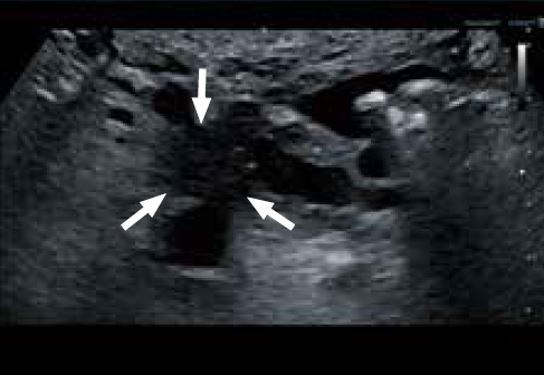

Рак підшлункової залози

Невеликі пухлини підшлункової залози часто важко виявити, оскільки підшлункова залоза розташована глибоко в черевній порожнині. Можливість візуалізації гіпоехогенної пухлини розміром 1,5 см в діаметрі наочно демонструє, що надширокосмуговий конвексний датчик забезпечує надзвичайну роздільну здатність і проникнення (рис. 3а). За допомогою датчика "2-в-1" можна отримати зображення з більш високим співвідношенням сигнал/шум (SNR). Можна чітко візуалізувати контур пухлини і розширення панкреатичної протоки та її гілок (рис. 3б).

a) Рак підшлункової залози

б) Розширення протоки підшлункової залози та однієї з її гілок

Рисунок 3. Рак підшлункової залози